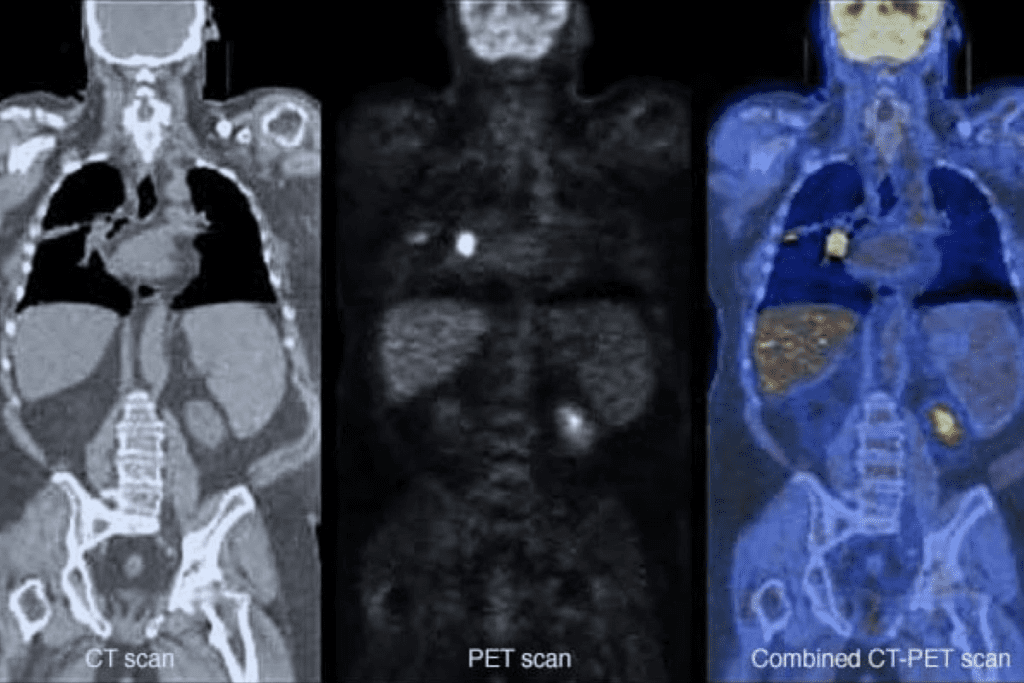

How PET Scans Differ from Other Imaging Tests

PET scans are different from CT and MRI scans. While CT and MRI show body structures, PET scans look at how tissues work. This makes PET scans great for:

By mixing PET scan data with other images, doctors get a full picture of a patient’s health. This leads to better diagnoses and treatment plans.